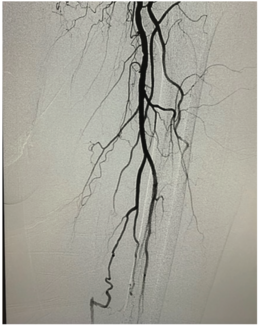

The patient is a 79-year-old male with a history of chronic atrial fibrillation, peripheral arterial disease with previous iliac stents, venous insufficiency, hypertension, and lifestyle-limiting claudication, with the left leg more...